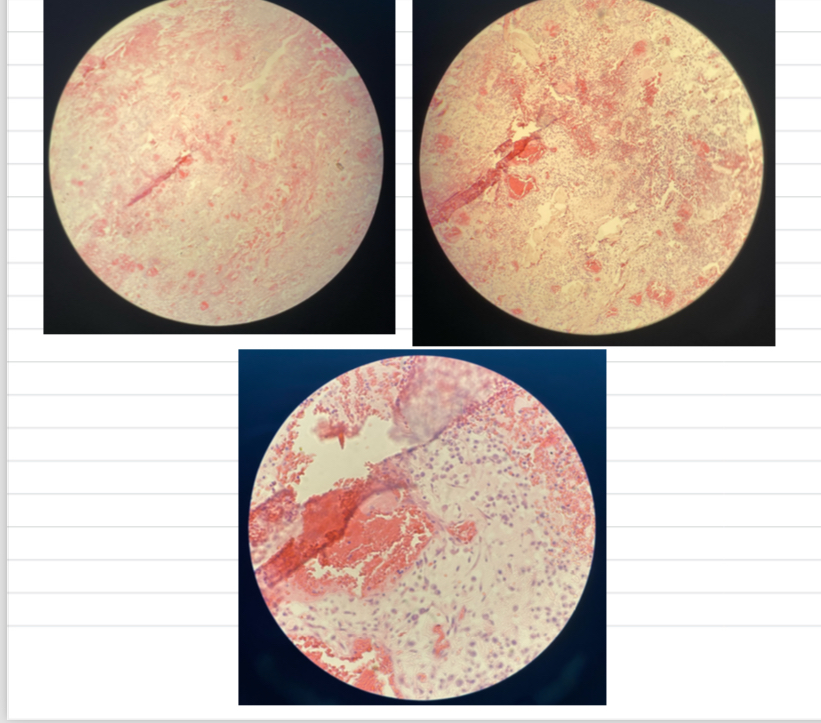

Infectious Canine Hepatitis (ICH)

- hepatic necrosis

- congestion + inflam infiltrate

- intranuclear viral inclusion bodies (basophilic)

Canine Distemper Virus (CDV)

- interstitial pneumonia => narrow lumen

- bacterial/catarrhal-purulent bronchopneumonia => inflam cells in bronchioles + alveoli

- intracellular viral inclusion bodies

Feline Panleukopenia.... catarrhal inflam of intestinal mm

- looks like worm on slide

- fibrin accumulation + crypt necrosis

- hemoarrhages + inflam cells

- basophilic intranuclear inclusion bodies in crypt epi